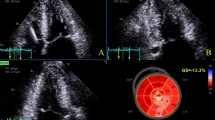

Tables 1 and 2 summarize the differences in patient characteristics and echocardiographic data among the three groups of impaired LS patterns. Through the groups, reduced LVEF and enlarged LV end-diastolic dimension were consistent with DCM characteristics. The GLS value was low. The RapLSI was not correlated with EF and GLS (Fig. 1A, B). The RapLSI was widely distributed, particularly among the low GLS values. Consequently, GLS in the scattered/homogeneously impaired group differed from that in the other groups. Figure 1C shows the representative LS patterns of the three groups. In the patients in the apical relatively preserved group, new-onset HF was more often, but LVEF was more reduced. In contrast, patients in the apical relatively-impaired group tended to have more RV-paced rhythms compared with the other groups. No significant differences were observed in atrial fibrillation, medication, left and RV diastolic dimensions, or both systolic and diastolic wall stress on the left ventricle among the groups. Although there were some differences in clinical data between the two institutions (Supplemental Table 1 and 2), the differences in clinical characteristics among the three LS distribution groups after adjustment for the examined institution were consistent with those before adjustment (Tables 1, 2). In evaluating the associations between LS and HF duration, we observed a poor but significant correlation of HF duration with that of an apical LS (p = 0.02, r = 0.20) but not with the basal (p = 0.17) and mid-LS (p = 0.26). More impaired GLS in all patients tended to be correlated with longer HF duration (p = 0.07). In a limited number of patients with a scattered/homogeneous pattern, a weak association between the GLS and HF duration was observed (p < 0.01, r = 0.32).

A Relationship between the RapLSI and EF. There is no significant correlation. B Relationship between the RapLSI and GLS. There is no significant correlation. However, the RapLSI has considerably dispersed in the lower part of the GLS. C The typical LS bull’s eye map of the apical relatively preserved, scattered/homogenously impaired, and apical relatively-impaired groups in severely decreased GLS. GLS, global longitudinal strain; LS, longitudinal strain; RapLSI, relative apical longitudinal strain index; and LVEF, left ventricular ejection fraction